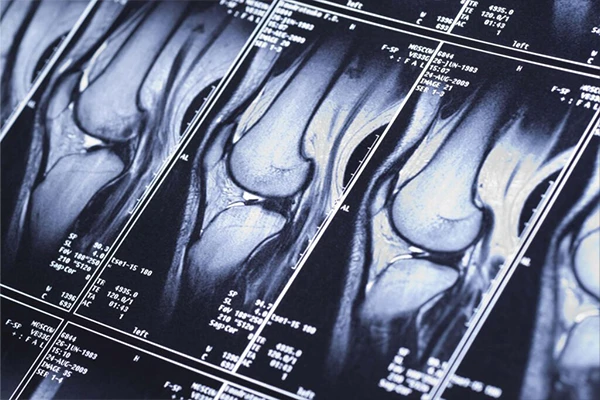

The Principles of Magnetic Resonance Imaging (MRI)

Explore how MRI uses powerful magnets and radio waves to generate sophisticated images of soft tissues.

Understanding MRI Sequences: A Guide to T1, T2, FLAIR, and DWI

A deep dive into common MRI sequences, what tissues they highlight, and their clinical uses.